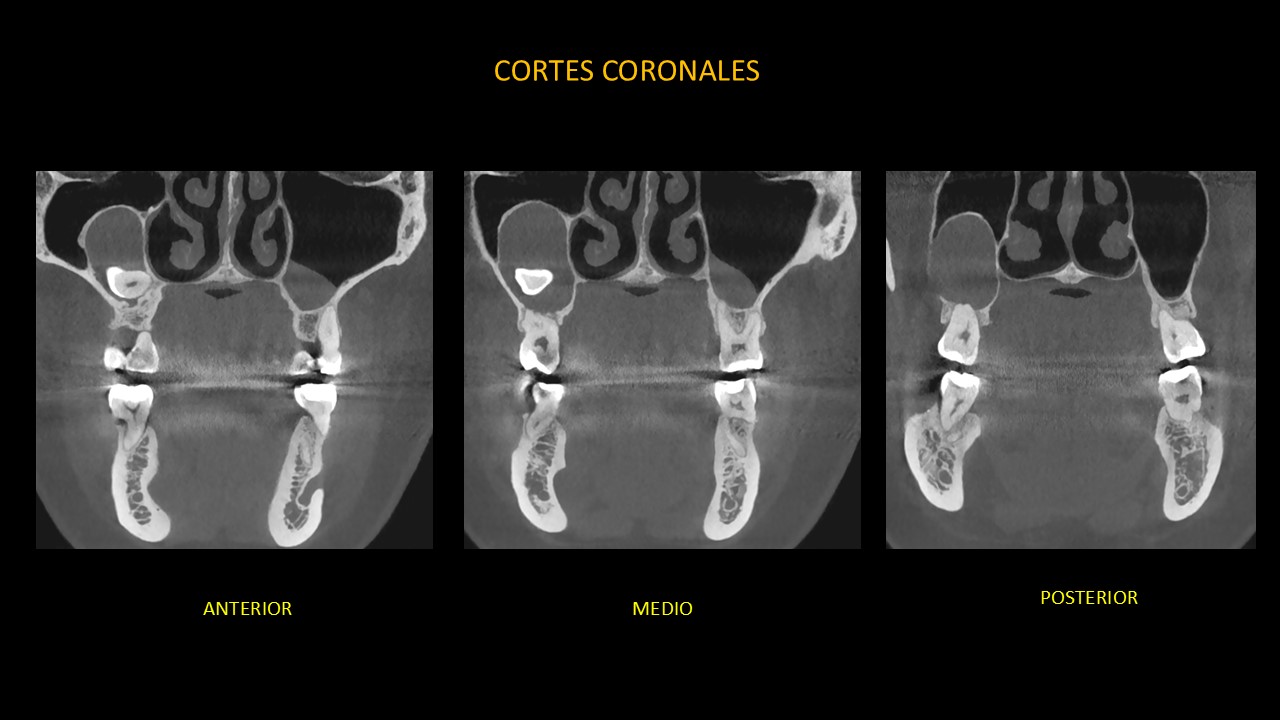

Figura 3

En la vista coronal (Figura 3), se observa la extensión de la lesión desde el tercio medio del seno maxilar derecho hasta el tercio apical de las piezas 17, 16; así como el desplazamiento del piso de seno maxilar derecho hacia cefálico.